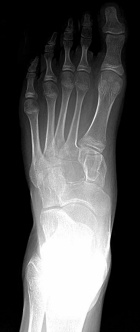

15 year old male with a left foot mass x >1yr.

It has recently grown in size and he has discomfort putting on hockey skates.